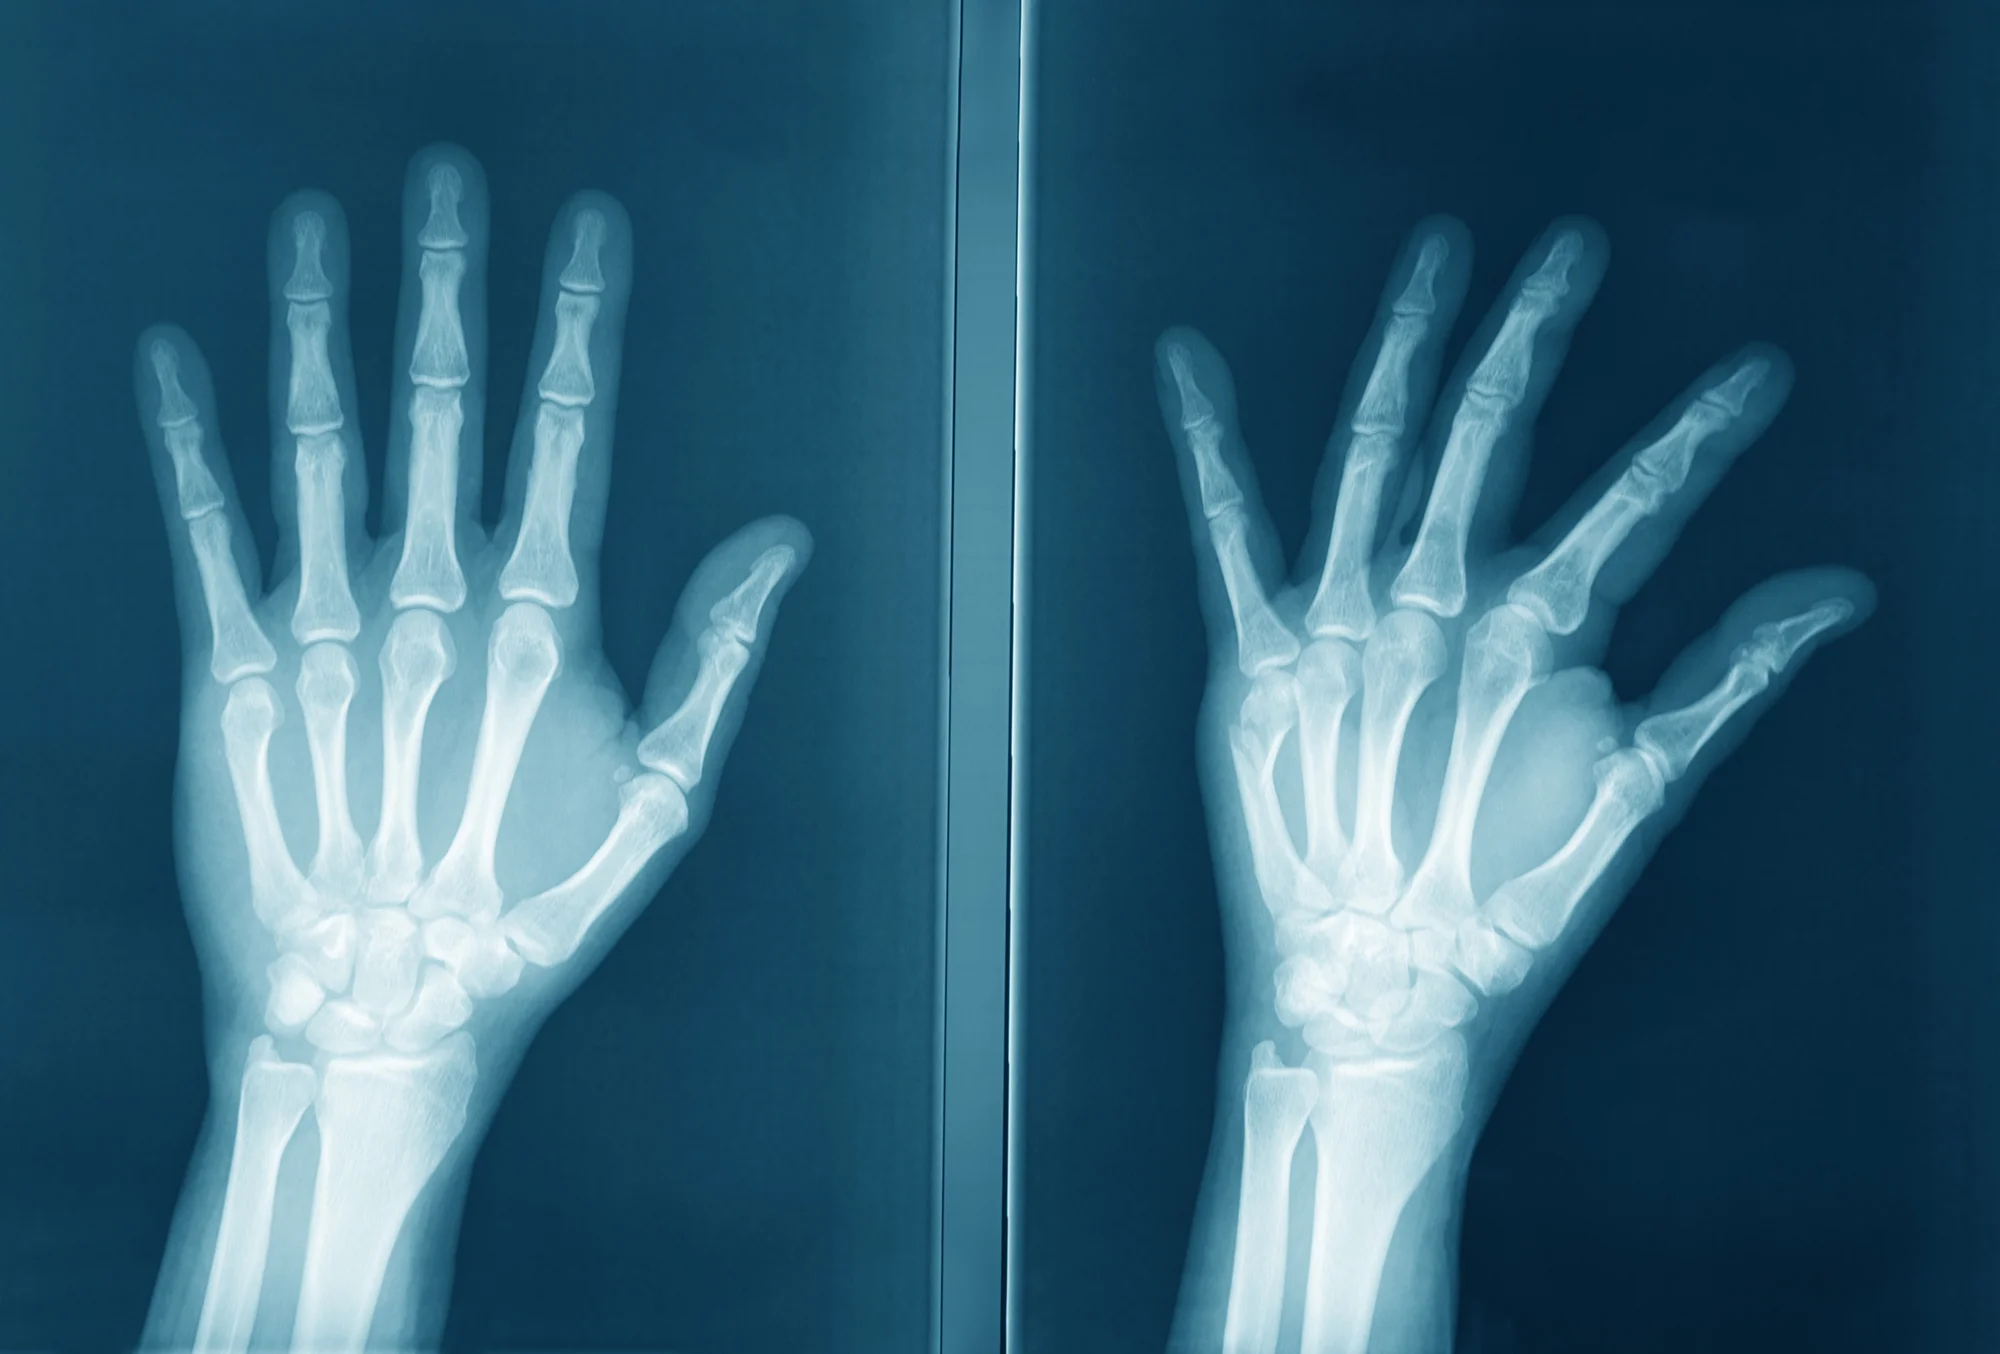

The commonest bone tumour is an enchondroma. This is an area of bone that has abnormal cartilage cells. The xray below shows that the middle phalanx of the little finger (arrowed) has a different texture to that of the adjacent ring finger. This tumour normally may be simply treated by curettage (scraping out the tumour).